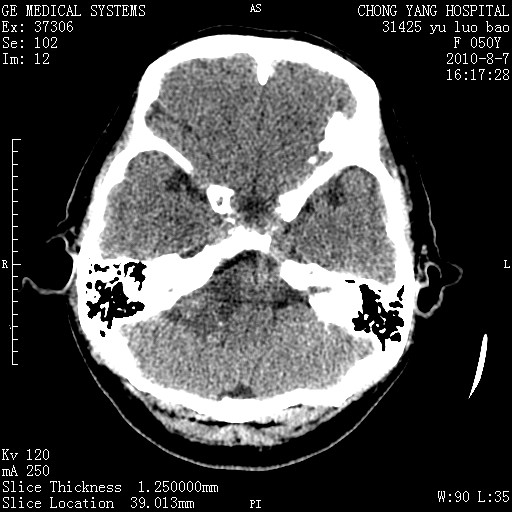

标题: CT28285:听力下降一年,头昏。 [打印本页]

标题: CT28285:听力下降一年,头昏。

右侧桥小脑角区占位--听神经瘤,建议增强或mri检查。

右侧桥小脑角去等密度占位,右侧内听道扩大、骨质吸收,考虑:右侧听神经瘤,建议增强检查。

右侧内听道扩大、骨质吸收,中脑受压左移,考虑:右侧听神经瘤,建议增强检查。支持!

右侧桥小脑角区等密度占位,内耳道扩大,听神经瘤